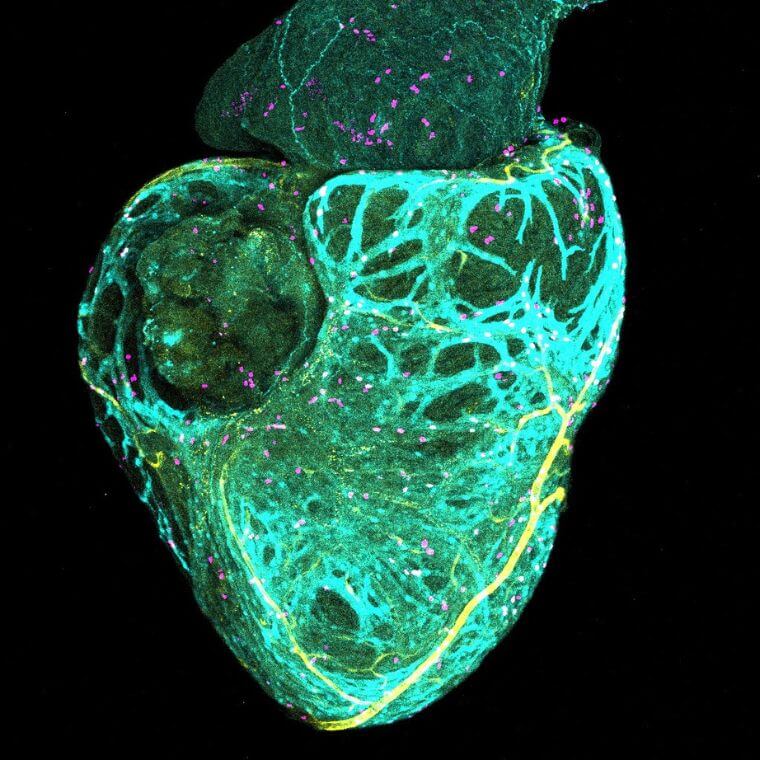

À gauche: Cette vue du ventricule du poisson zèbre révèle l’apparition des futurs vaisseaux coronaires, rendus visibles grâce à deux lignées fluorescentes qui marquent les cellules endothéliales en cours de formation; au centre: Grâce à différents marqueurs fluorescents, on peut voir simultanément les vaisseaux coronaires naissants, les cardiomyocytes et les cellules se multipliant, illustrant la croissance synchronisée du réseau vasculaire et du muscle cardiaque. À droite: Cette vue du ventricule met en évidence la progression parallèle des vaisseaux coronaires et du tissu musculaire cardiaque, chacun marqué par une couleur fluorescente distincte qui permet de suivre leur maturation conjointe.

L’étude, dont les résultats sont publiés dans la revue Development, combine l’imagerie 3D et des lignées génétiques de poissons zèbres afin de déterminer où, quand et comment les vaisseaux coronaires se forment et guident la maturation des cellules du muscle cardiaque.

En analysant le développement vasculaire micromètre par micromètre, dès une taille corporelle de sept millimètres, l’équipe a produit des images 3D d’une précision remarquable. Grâce à cette approche, elle a pu suivre la formation du réseau coronaire: émergence des premières pousses vasculaires, ancrage, croissance, ramification et maturation en un réseau pleinement fonctionnel.